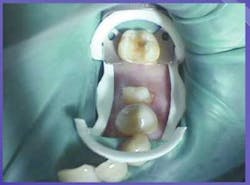

With the newer matrix systems on the market, placement of a matrix using dental dam should not present a problem. Systems that do not use a tofflemire will less likely run interference with the mesial extensions on a winged clamp. Contoured sectional matrix systems used with either G-Rings® or Bitine® Rings permit easy access to the restorative site, even with the dental dam in place (figure 5). If the last tooth in the arch requires an interproximal restoration, use a flat-jawed clamp rather than a curved-jawed clamp, as the curved-jawed clamp will not allow the matrix to seat fully. If a distal preparation is required on the last tooth, rotate the clamp so its bow is on the mesial instead of the distal of the tooth. Retract the distal dental dam with the end of a mirror handle and use a surgical-length friction grip bur to gain access to the distal of the tooth. Once the distal preparation is completed, reposition the clamp to its proper position.